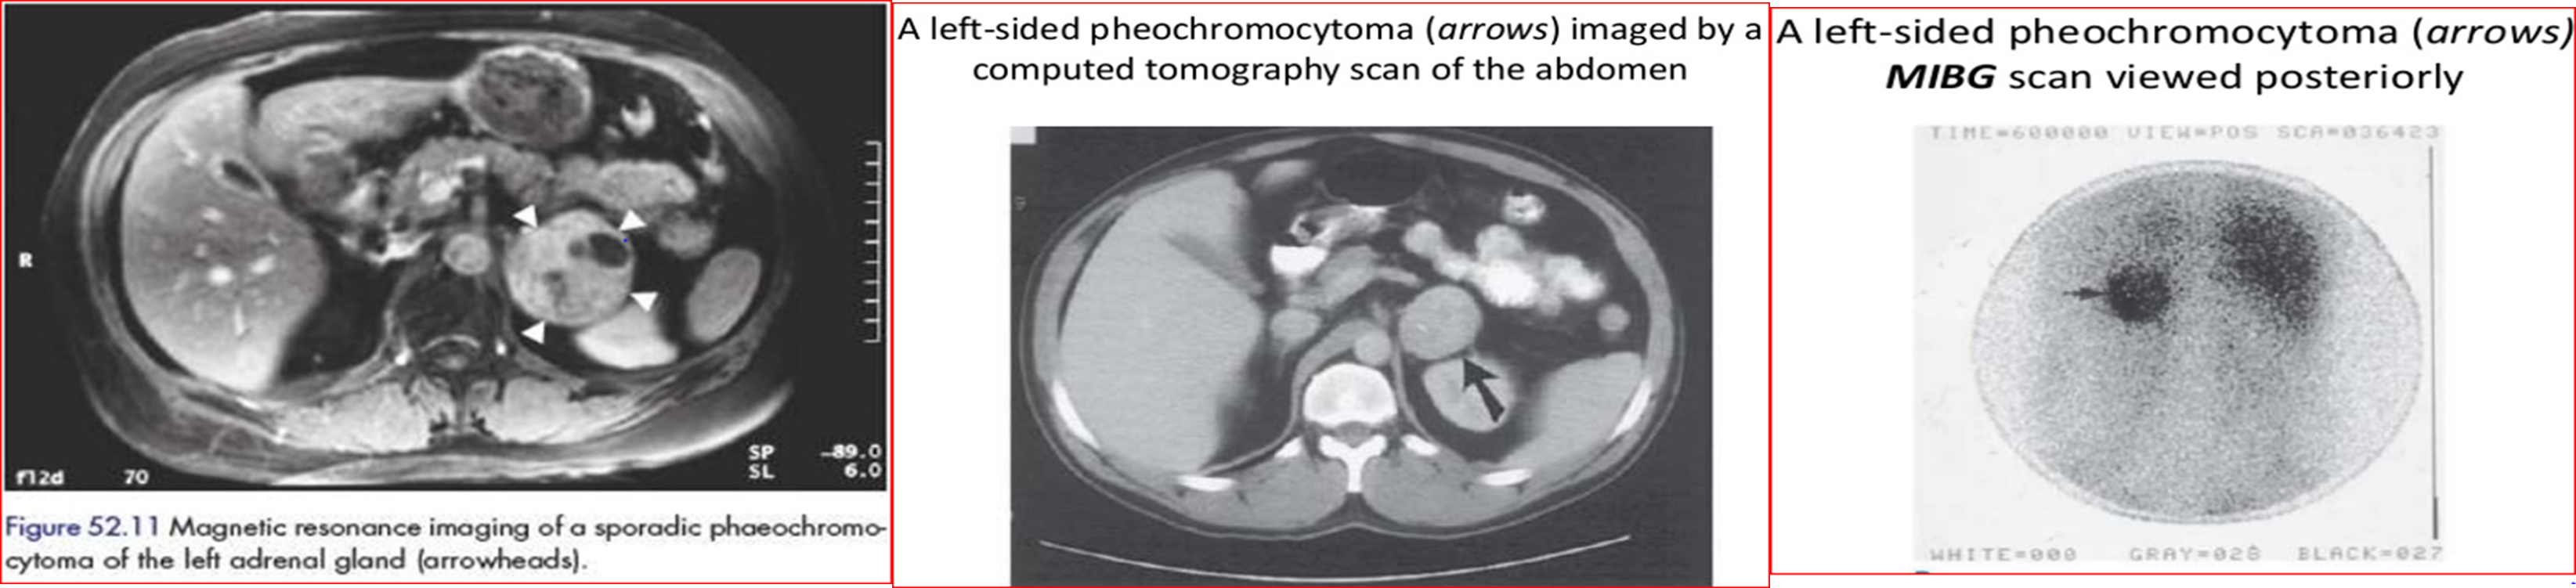

- CT/MRI to locate tumor/ (MIBG scan)

An MIBG scan iodine-123 meta-iodobenzylguanidine

is commonly used for the detection of neuroendocrine tumors, such as neuroblastoma and pheochromocytoma.

It can also aid in the detection of carcinoid and medullary thyroid carcinoma